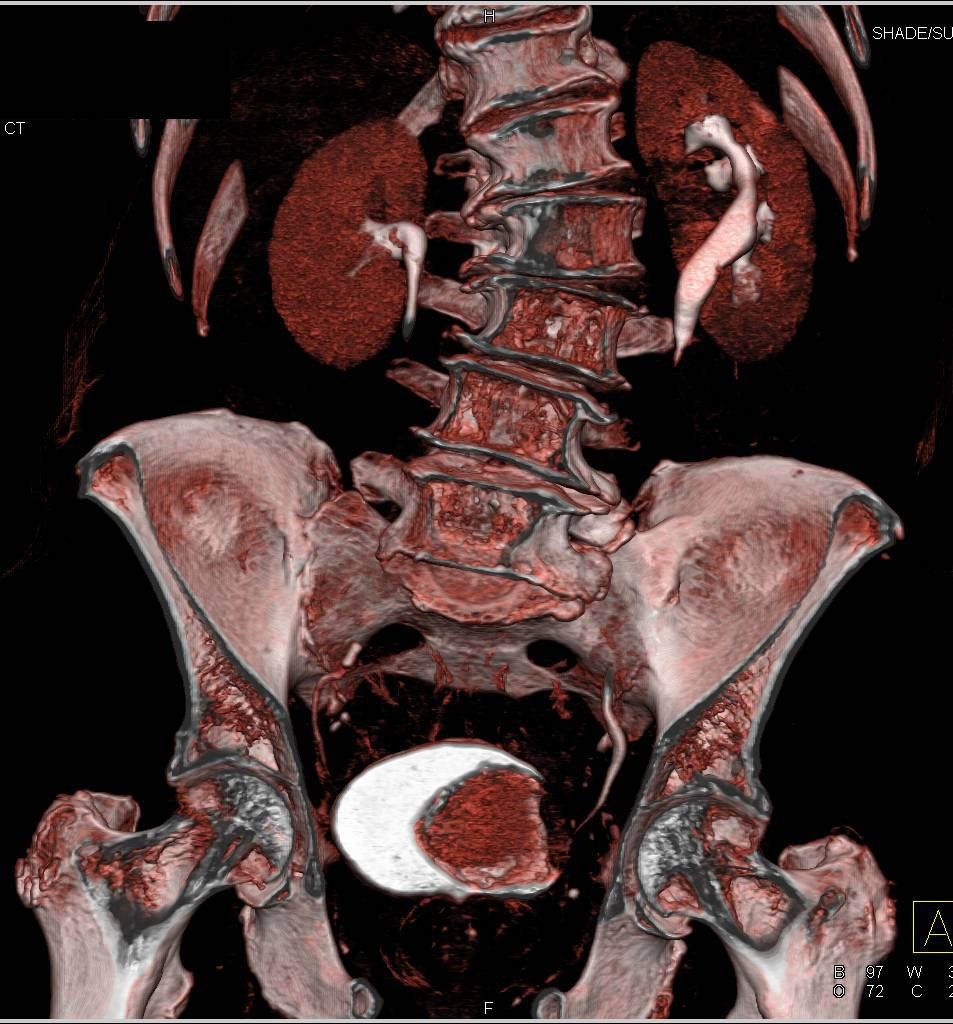

Njen prosperitet leži u tome da nakon volumnog snimanja aksijalnim presjekom softverski paketi omogućavaju brojne naknadne rekonstrukcije, a samim tim i sagitalne, koronarne i kose presjeke tijela, te 2D i 3D rekonstrukcije. Prije svake pretrage podešava se odgovarajući protokol snimanja, vrijeme, količina kao i brzina injiciranja intravenskog kontrastnog sredtsva.

Primjer ispitivanja hematurije CT urografijom kroz slučajeve!

Slučaj 1. Karcinom urotelnih ćelija.

Slučaj 2. Karcinom mokraćne bešike.

Slučaj 3. Kamenci u bubrezima